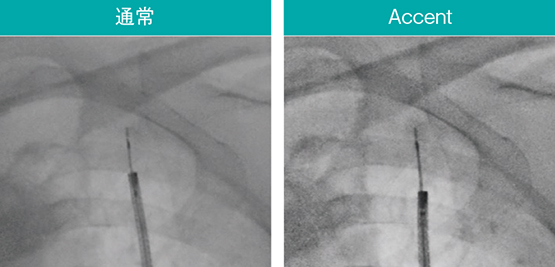

内視鏡検査に用いるデバイスは通過性や柔軟性が優先され、透視下での視認性に課題がある製品もある。Ultimax-i の新画像処理条件「Accent」は、ガイドシースや生検針などのデバイスや関心領域を強調し、より手技がしやすい環境を提供する。実際の透視像(図7〜9)でも、Accent適用により腫瘤やEBUSプローブ、ガイドシース、ブラシなどのデバイスが明瞭に確認できる。

図7 AccentによるEBUSプローブや関心領域の強調

スコープ:BF-MP290、EBUS:UM-S20-17S(オリンパス社製)

図8 Accentによる鉗子や関心領域の強調

スコープ:BF-MP290、生検鉗子:FB-433D(オリンパス社製)